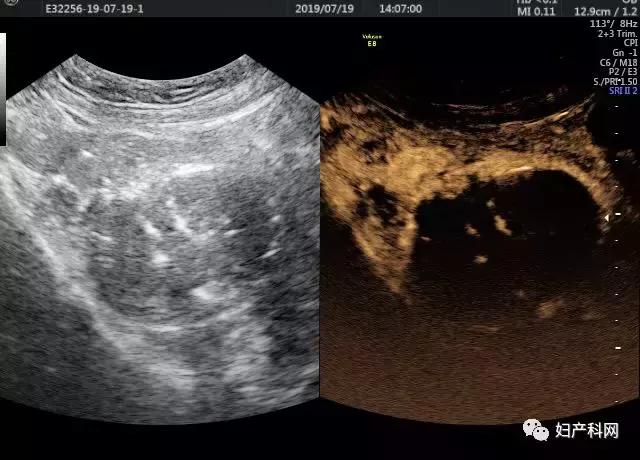

宫颈肌瘤术后超声造影